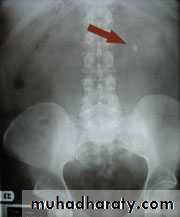

Urinary calculiMay be asymptomatic

70- 80 % are calcified and show varying densities on plain film

20-30 % are radiolucent

The larger stone assume the shape of the PCS staghorn calculus

Plain film exam of the urinary tract ( KUB) is more sensitive than US for detecting opaque renal and ureteric stone .Plain film is essential to be used as a preliminary film before injection of the contrast in IVU and should be examined carefully because even a large stone can be hidden within the opacified collecting system once contrast medium has been given.